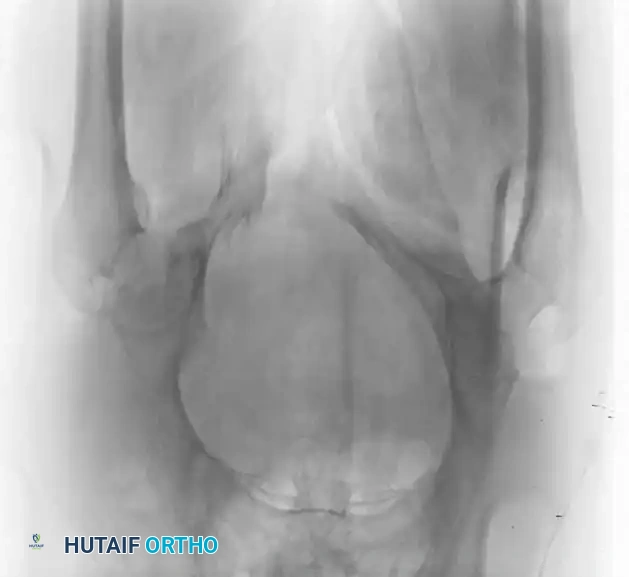

Radiographic Evaluation

Standard evaluation begins with an Anteroposterior (AP) pelvis radiograph. However, definitive surgical planning requires specialized views and advanced imaging.

• Inlet View: Directed 45 degrees caudad. Best evaluates anterior-posterior translation, internal/external rotation, and sacral impaction.

• Outlet View: Directed 45 degrees cephalad. Best evaluates vertical translation and sacral foraminal anatomy.

• CT Scan: The gold standard for evaluating posterior ring injuries, sacral dysmorphism, and preoperative planning for percutaneous fixation.